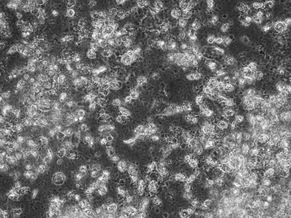

Účinok vírusu na modelové línie a normálne ľudské fibroblasty ukazujú mikrofotografie tkanivových kultúr 24, 48 a 96 hodín po aplikácii vírusu a kontrolnú kultúru odpovedajúcu 96 hodinám (obr. 2 a, b, c, d). Účinok vírusu v desiatkovom riedení na bunky mozgového nádoru hodnotený MTT testom ako % negatívnej kontroly (priemer s.d.) ukazuje obr. 3. Reovírus serotypu 3, kmeň Dearing, mal silné cytotoxické účinky na všetky testované línie s výnimkou normálnych ľudských fibroblastov.

Obr. 2

2Amedulloblastom kultivovaný 96 hod s reovirusom. 2Bnormálne ľudské fibroblasty kultivované 96 s reovirusom.

2C – medulloblastom kultivovaný 96 hod bez reovirusu. 2Dnormálne ľudské fibroblasty kultivované 96 bez reovirusu.